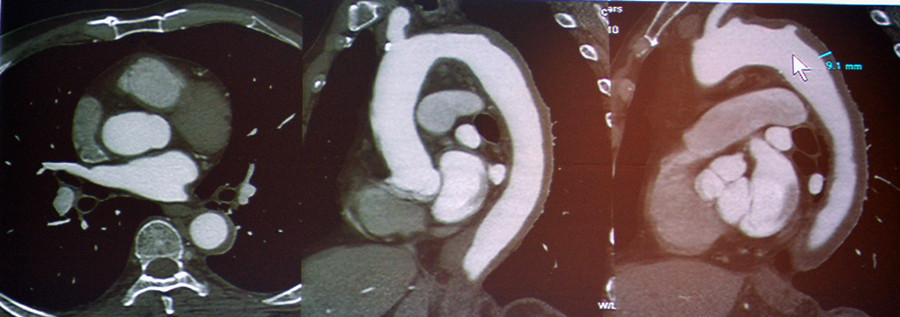

急性冠脉综合征:TRO可清晰地显示斑块、狭窄、闭塞和心肌缺血等病变。

图2-3 急性冠脉综合征